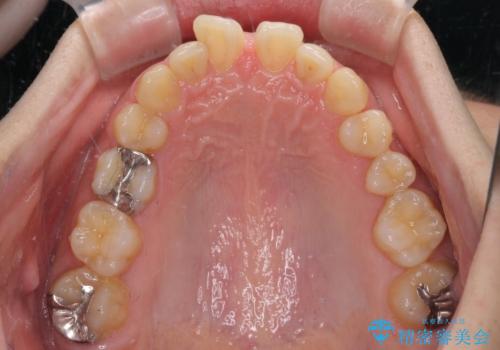

- 前歯の隙間を気にして来院された患者様です。

下顎前歯が見えなくなるくらいに深い咬み合わせであり、さらに上顎の正中が開くほど下の前歯が突き上げている状態でした。

奥歯は手前に倒れてしまっているため、後方に起き上がらせることで深い咬み合わせ・ディープバイトを改善する必要があります。

右上と左下は永久歯が欠如しており、大きさの大きく異なる乳歯が残存していたため、奥歯の咬み合わせを構築するために苦労しました。